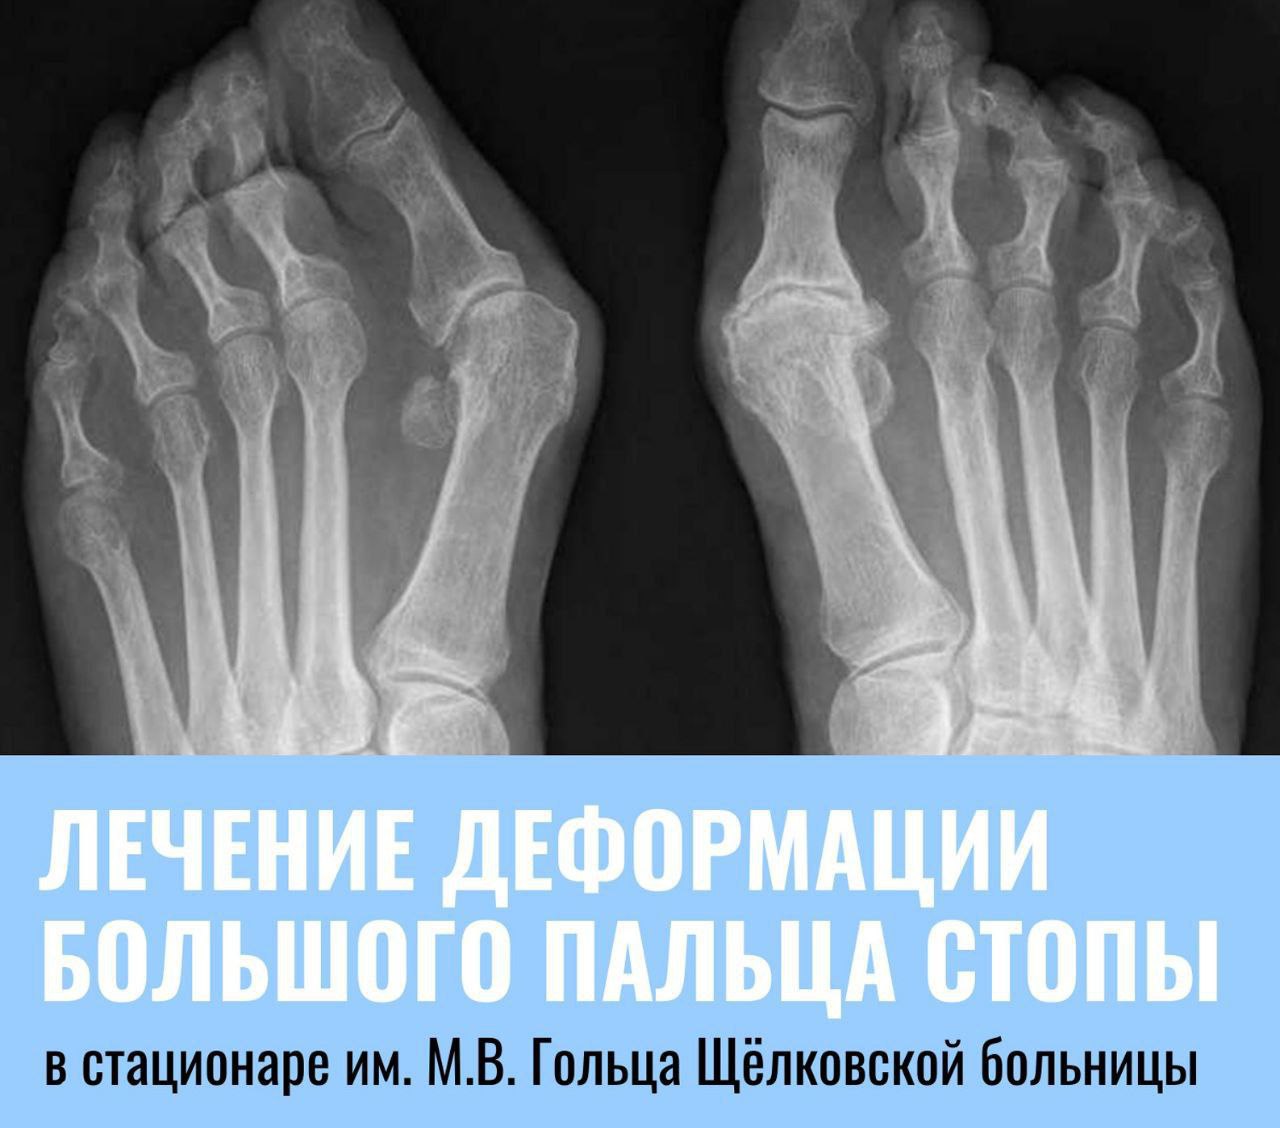

В обособленном подразделении им. М.В. Гольца Щёлковской больницы с недавнего времени проводят высокотехнологичные операции по коррекции вальгусной деформации большого пальца ноги или так называемой «косточки» на ноге. Преимуществами хирургического лечения, по сравнению с консервативными методами коррекции, является его эффективность — результат виден сразу после операции. 👠 Как отметил оперирующий врач-травматолог-ортопед Щёлковской больницы Даниил Лапин, данная патология может возникнуть как из-за ношения неудобной обуви, так и генетической предрасположенности, и чаще всего встречается у женщин старшего возраста. Причиной обращения за помощью к специалистам становятся физические неудобства, выраженный болевой синдром или эстетический дискомфорт. Операция проводится в плановом режиме. Само вмешательство проходит под общим или спинальным наркозом и занимает около часа. Для коррекции врачи используют современные высокопрочные импланты. Восстановление пациента после такой процедуры занимает около семи дней. 📄 Хирургическая коррекция большого пальца стопы выполняется за счет средств ОМС. Направление на консультацию к специалистам стационара им. М.В. Гольца пациенты могут получить в поликлинике по месту прикрепления у врача-травматолога. 📍 Консультации в стационаре проходят каждую пятницу с 14:00 до 16:00 по адресу: г. Фрязино, ул. Московская, д. 7, корп. 5, каб. 313. Источник: Щёлковская больница |